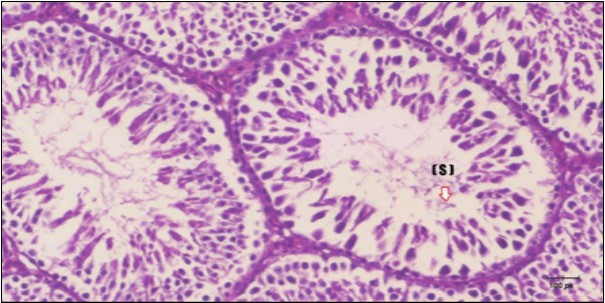

Testis Histopathological Observations

Histological examination of control rats' testis showed normal histological structure of the seminiferous tubules with an increase in the spermatogonia and other spermatocytes compared with the diabetic rats which showed an obvious decrease in the count of germinal cells generally and sloughing of germ cell in the lumen of seminiferous tubules in addition to absence of the mature sperms (Figure 3 and Figure 4). Rats tested of Fenugreek group and those treated with Glimepiride (Figure 5 and Figure 6) presented an increase in the number of spermatogenic cells and mature sperms with few focal necrotic cells. Whereas the combination therapy group showed normal histological structure of the seminiferous tubules with normal spermatogonia, presence of ledying cells and more mature of sperms (Figure 7). STZ reduced testosterone production, suggesting a decrease in the function of both Leydig (testosterone producing cell) and Sertoli (spermatogenesis) cells, which might be caused by a reduction in insulin secretion. These changes are probably due to increased Reactive Oxygen Species (ROS) production by accelerated Advanced Glycation End Products (AGE) formation 31 hexosamine and Protein Kinase C pathway. The administration of Fenugreek seeds to diabetic rats significantly decrease of sperm shape abnormality and improve the sperm count 32. Glimepiride reduced sperm abnormality and increased testis weights and sperm count by its antioxidant action 30. The potential protective efficacy of Fenugreek seed extract when added to Glimepiride was observed on reproductive systems.

Figure 4.Photomicrogragh of testis section of diabetic rat showing the sloughing of germ cells towards lumen of seminiferous tubules, absence of spermatozoa with low height of germinal epithelium and congested wide interstitial tissue (star). (H&E) (40x).